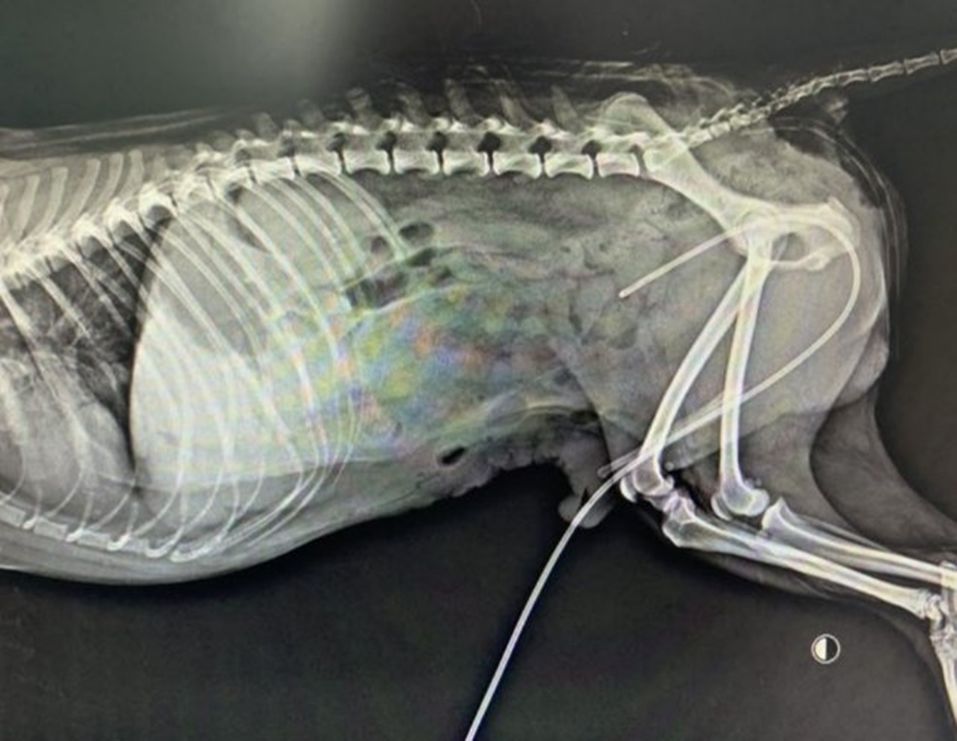

一例犬尿道多处破裂腹壁疝修复的病例分享

扩大疝环图11-669 在这只动物,同时使用了腹部和腹股

请输入图片描述 疝气是腹部的脏器从自然孔或病理性破裂到皮下或